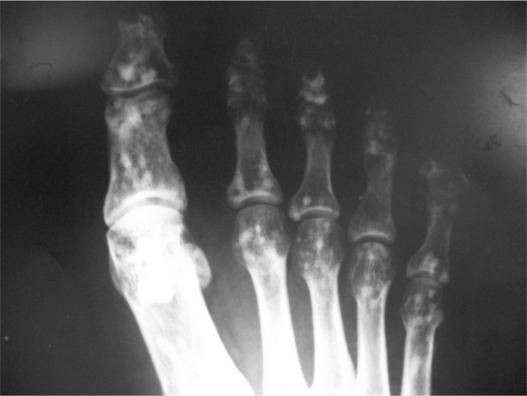

Osteopoikilosis is a rare asymptomatic sclerosing bony dysplasia of benign origin. It is usually found incidentally on radiological examinations. Familial occurrence indicates a genetic milieu with autosomal dominant pattern. Here, we present a case report of a young woman suffering from pelvic pain due to osteopoikilosis (OPK). The same disorder was later found in her son and daughter.

骨斑点症是一种罕见的良性起源的无症状硬化性骨发育异常。通常在影像学检查中偶然发现。家族性发病提示存在常染色体显性遗传模式的遗传背景。在此,我们报告一例因骨斑点症(OPK)导致骨盆疼痛的年轻女性病例。后来在她的儿子和女儿身上也发现了同样的病症。